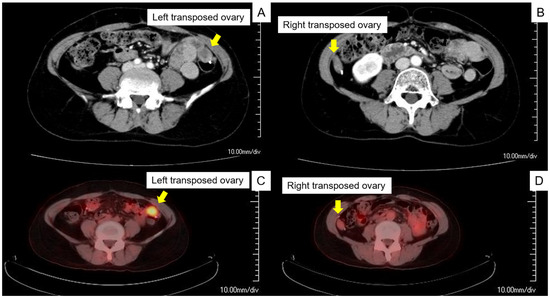

Surgical Management for Transposed Ovarian Recurrence of Cervical Cancer: A Systematic Review with Our Experience

In early-stage cervical cancer, ovarian metastasis is relatively rare, and ovarian transposition is often performed during surgery. Although rare, the diagnosis and surgical approach for recurrence at transposed ovaries are challenging. This study focused on the diagnosis and surgical management of transposed ovarian [...] Read more.

In early-stage cervical cancer, ovarian metastasis is relatively rare, and ovarian transposition is often performed during surgery. Although rare, the diagnosis and surgical approach for recurrence at transposed ovaries are challenging. This study focused on the diagnosis and surgical management of transposed ovarian recurrence in cervical cancer patients. A 45-year-old premenopausal woman underwent radical hysterectomy, bilateral salpingectomy, and pelvic lymphadenectomy following postoperative concurrent chemoradiotherapy for stage IB1 cervical cancer. During the initial surgery, the ovary was transposed to the paracolic gutter, and no postoperative complications were observed. Ovarian recurrence was diagnosed using positron emission tomography–computed tomography, and a laparoscopic bilateral oophorectomy was performed. A systematic review identified nine women with transposed ovarian recurrence with no other metastases of cervical cancer, and no studies have discussed the optimal surveillance of transposed ovaries. Of those (n = 9), four women had died of the disease within 2 years of the second surgery, and the prognosis of transposed ovarian cervical cancer seemed poor. Nevertheless, three women underwent laparoscopic oophorectomies, none of whom experienced recurrence after the second surgery. Few studies have examined the surgical management of transposed ovarian recurrence. The optimal surgical approach for transposed ovarian recurrence of cervical cancer requires further investigation. Full article